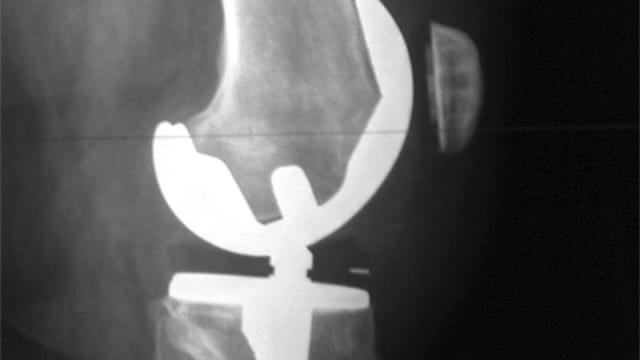

Patienten, die während der Pandemie eine Kniegelenk-Prothese brauchten, haben diese auch erhalten, allerdings unter Umständen erst etwas später. | Wikimedia

Während den Höhepunkten der Pandemie haben die Spitäler die Anordnungen der Behörden, nicht-dringliche medizinische Eingriffe einzuschränken, eingehalten.

Das führte während der ersten Welle in beiden Ländern zu einem markanten Rückgang bei der Implantation von künstlichen Knie-Gelenken. Im Vergleich zum Vorjahr wurden in beiden Ländern knapp zehn Prozent weniger Kniegelenk-Ersatz-Operationen durchgeführt. Vor allem in der Schweiz wurden diese Eingriffe aber nachgeholt.